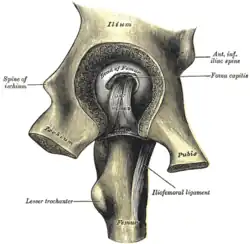

Becken (Pelvis)

Am Aufbau des Gegenstückes, der Hüftgelenkpfanne (Acetabulum), sind alle drei Beckenknochen beteiligt: Das Dach wird vom Darmbein (Os ilium) gebildet, das Schambein (Os pubis) begrenzt vorne (ventral) und das Sitzbein (Os ischii) hinten-unten (dorsokaudal) den Rand des Beckens mit seiner Vertiefung, das so genannte Acetabulum („Essignäpfchen“).

Stellt man sich die Pfanne als hohle Halbkugel vor, beträgt ihr Radius beim Menschen je nach Körpergröße etwa 2,7 Zentimeter. Eine bogenförmige Faserknorpellippe (Labrum acetabuli bzw. Limbus acetabuli) geht jedoch stellenweise über den Äquator der Halbkugel hinaus und umgreift regelrecht den Oberschenkelknochenkopf. Daher spricht man beim Hüftgelenk auch von einem Nussgelenk (Sonderform des Kugelgelenkes). Zum Schambeinloch (Foramen obturatum) ausstrahlend ist die Pfannenlippe hingegen unterbrochen (Incisura acetabuli), sodass sie eine halbmondförmige Gestalt annimmt. Dieser unterbrochene Teil der Pfanne wird von einem Querband (Ligamentum transversum acetabuli) überbrückt.

Bänder innerhalb der Kapsel

- Das Oberschenkelknochenkopfband (Ligamentum capitis femoris) verläuft von der Pfannengrube (Fossa acetabuli, genauer Incisura acetabuli) in einer kleinen Vertiefung im Oberschenkelknochenkopf (Fovea capitis femoris). Es hat keine mechanische Funktion, sondern beinhaltet eine Arterie, die den Hüftkopf versorgt (Arteria capitis femoris). Weitere Arterien, die den Hüftkopf versorgen, sind die Arteria circumflexa femoris lateralis und der Arteria circumflexa femoris medialis. Bei Pferden besitzt das Oberschenkelknochenkopfband eine Abspaltung (Ligamentum accessorium capitis femoris), welche sich am Schambein anheftet.

- Das quere Pfannenband (Ligamentum transversum acetabuli) verschließt die Lücke in der Hüftgelenkspfanne (Incisura acetabuli) und vervollständigt so die knöcherne Gelenkpfanne nach unten hin.